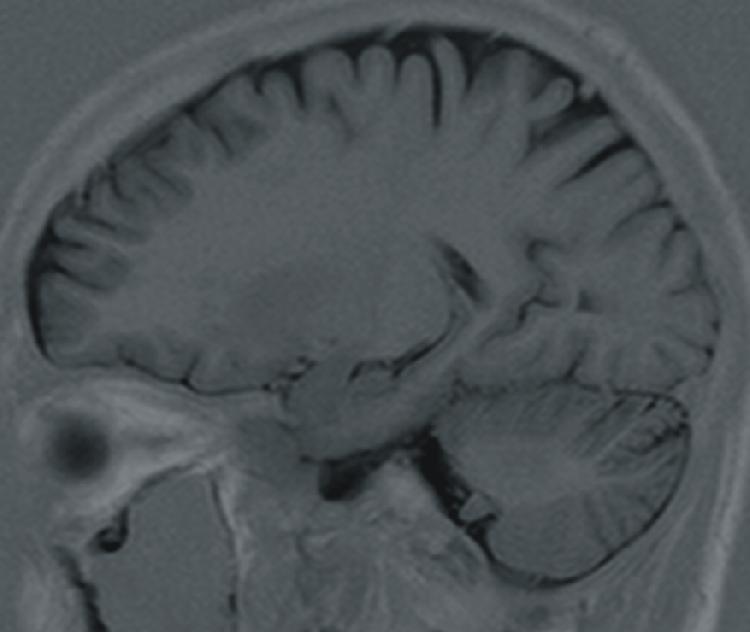

| Sulcus centralis |

| Insula |

| Claustrum |

| Putamen |

| Globus pallidus |

| Nucleus caudatus - corpus |

| Nucleus caudatus - cauda |

| Capsula externa |

| Capsula extrema |

| Ventriculus lateralis - pars centralis |

| Ventriculus lateralis - cornu temporale |

| Plexus choroideus |

| Hippocampus |

| Corpus amygdaloideum |

| Fimbria hippocampi |

| Cerebellum |